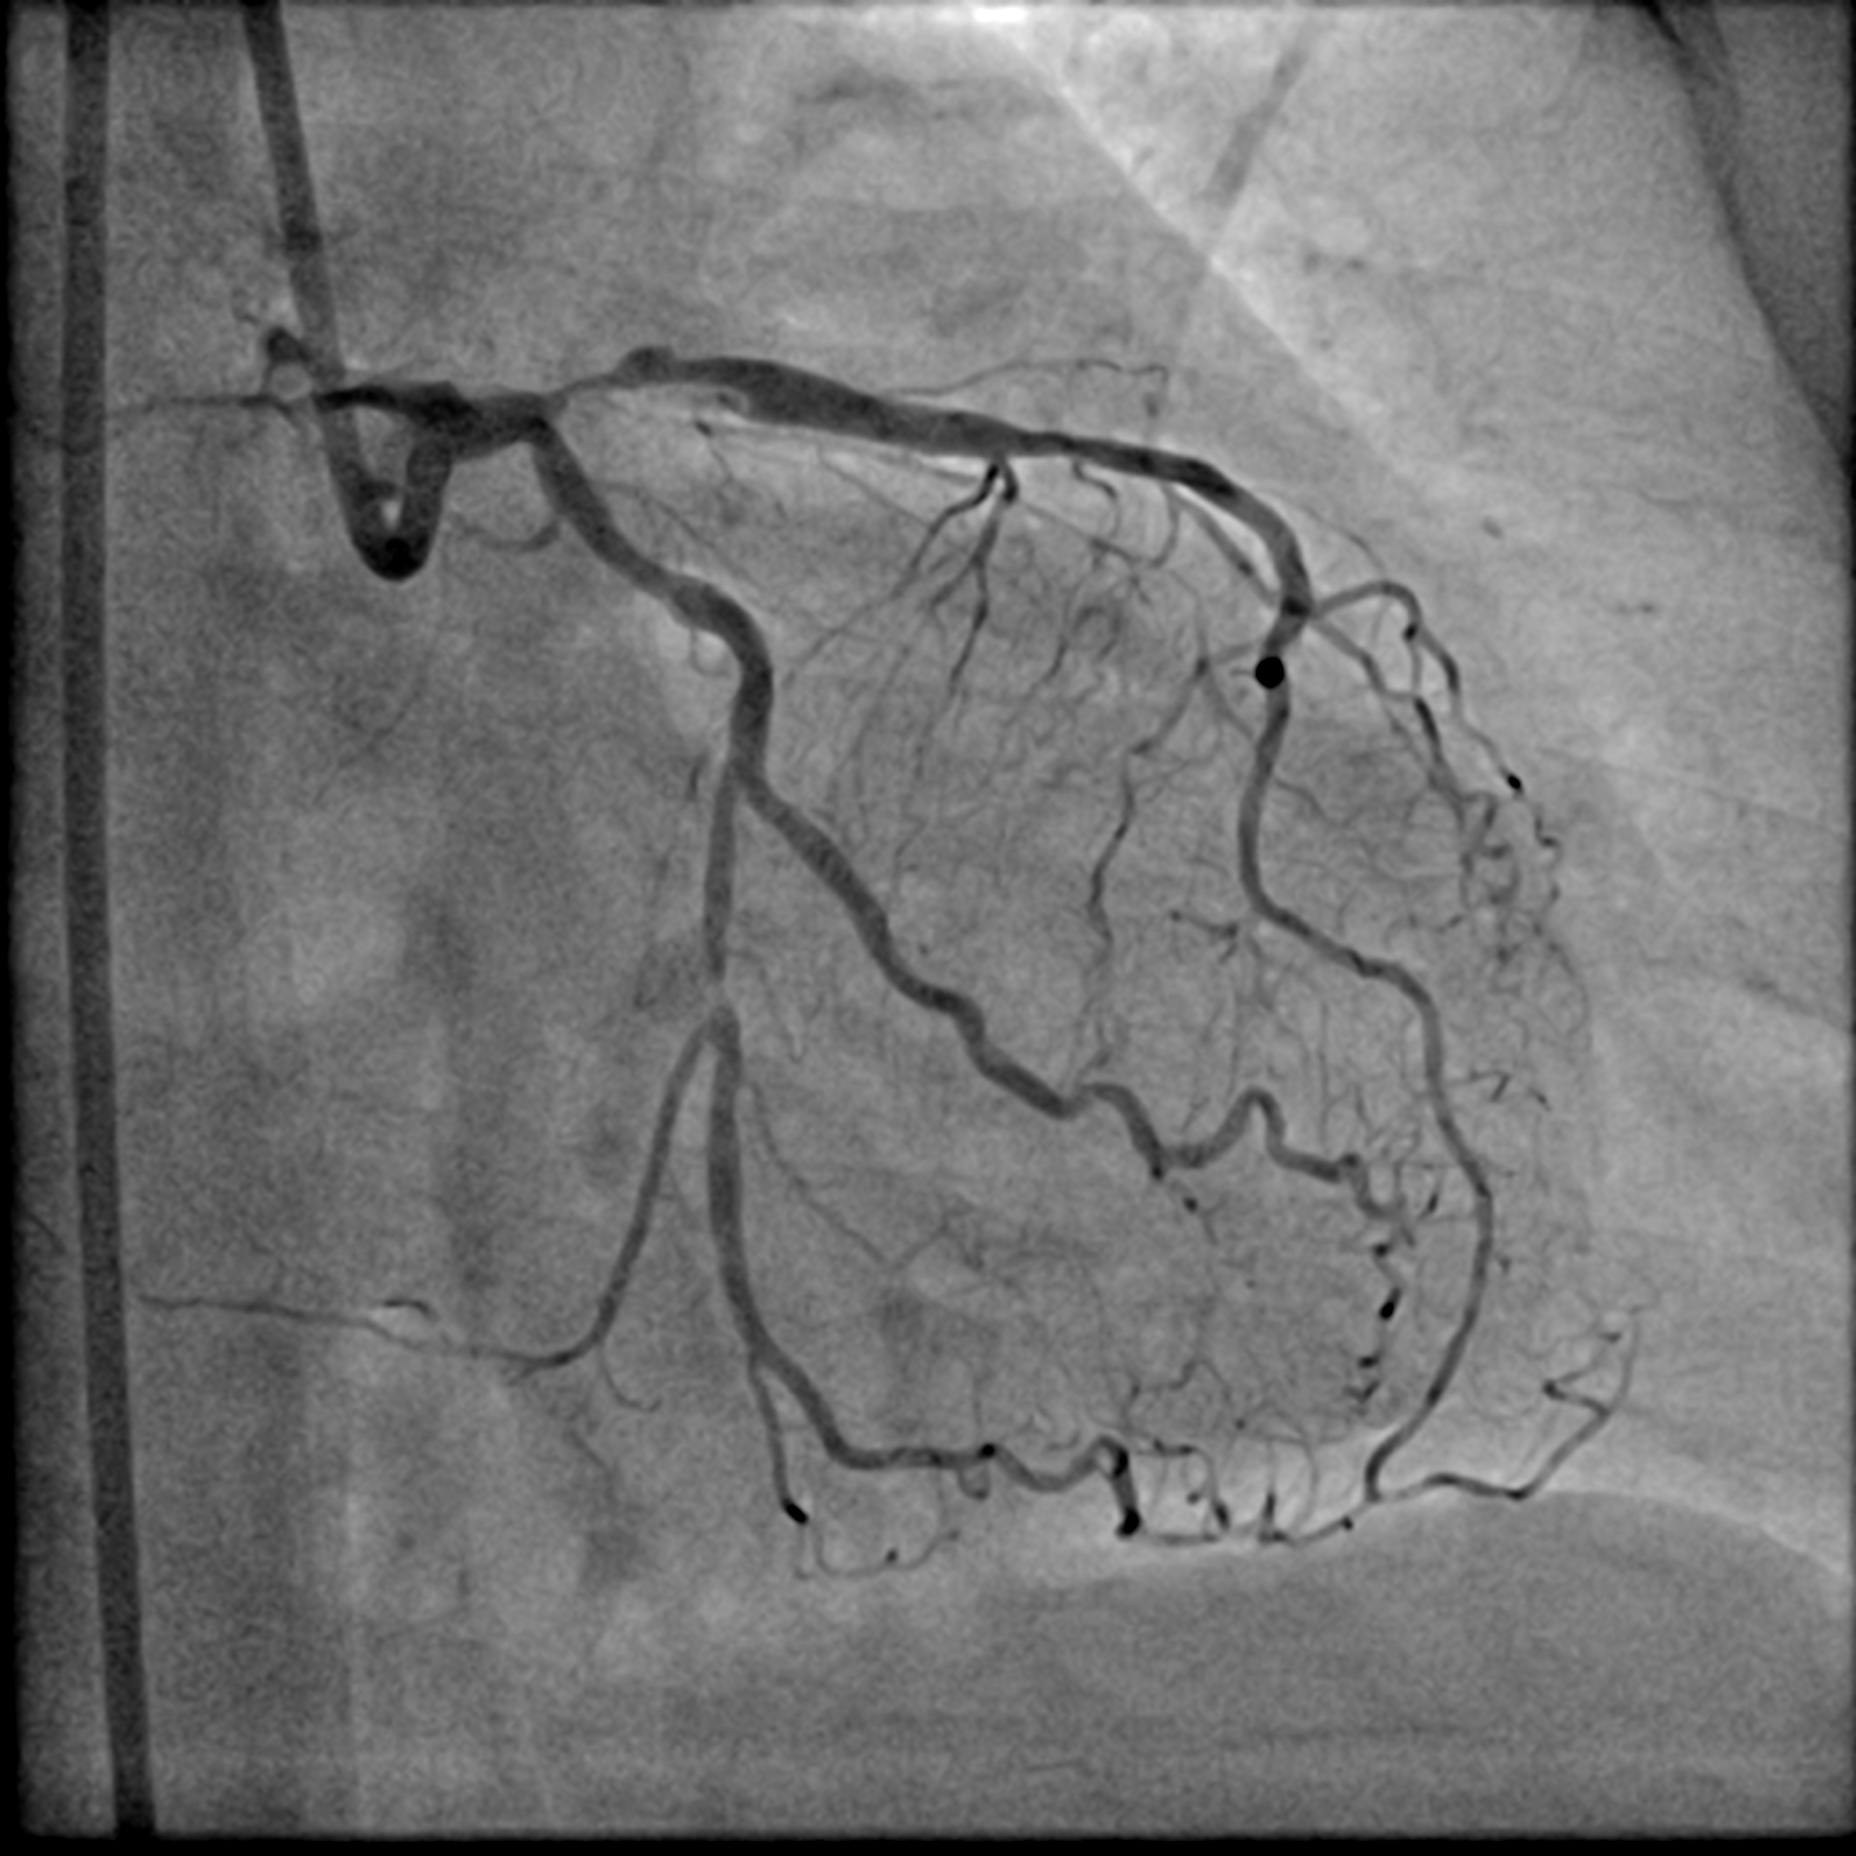

A LMS hybrid therapy was planned. A 7 Fr EBU 3.5 catheter was engaged to the LMS. Two workhorse wires were placed in the distal LAD and LCx. The LAD was pre-dilated with a 3.5 mm cutting balloon without facing significant difficulty. However, pre-dilatation of the LCx with a 3.5 mm cutting balloon was unsatisfactory due to the calcium nodule. This was overcome with lesion preparation using a 3.5 mm Lithix balloon. Adequate lesion preparation was confirmed with repeated angiography and IVUS assessment. The ostial LCx was treated with a 3.5 x 20 mm Drug-Coated Balloon (DCB), while the LMS-LAD segment was stented with a 4.0 x 22 mm Drug-Eluting Stent (DES). Proximal Optimization Technique (POT) was performed using a 4.5 mm NC balloon, and the stent in the LAD segment was post-dilated with a 4.0 mm NC balloon. Repeated angiography revealed a Type B dissection with a narrowed lumen in the LCx, necessitating stenting. The LCx was re-wired using a dual-lumen catheter from the inner frame of the LMS stent. The stent strut was opened with a 2.0 mm balloon and a 3.5 mm NC balloon. T-stenting of the ostial LCx was performed with a 3.0 x 26 mm DES, utilizing a balloon catheter in the LAD wire as a marker. The LCx stent was first post-dilated with a 3.5 mm NC balloon. Subsequently, the Kissing Balloon Technique (KBT) was performed with a 4.0 mm NC balloon in the LAD and a 3.5 mm NC balloon in the LCx. Finally, repeated POT was completed with a 4.5 mm NC balloon in the LMS.

LCA final AP cran.mp4

LCA final AP Caud.mp4